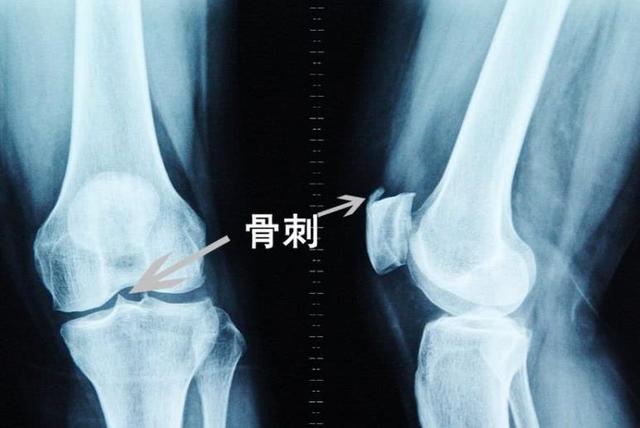

【骨质增生】

很多老年人都患有骨质增生,也就是我们大家常说的骨刺,如果患有骨质增生,身体会出现很多不适症状。

尤其是在阴雨天,更是疼痛难忍,这类疾病一旦患上,基本没有什么好的办法可以彻底将其拔除,只能通过自身的保养,平时可以加强锻炼,多多运动。